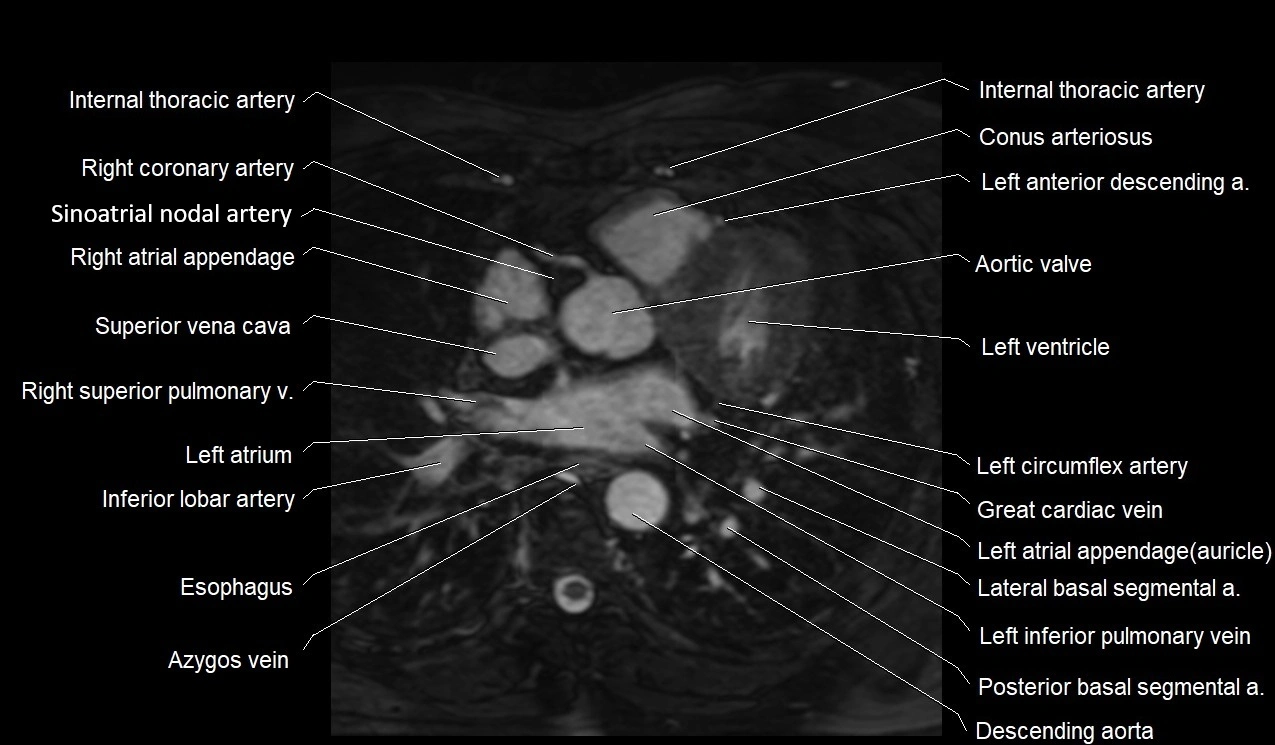

MRI image